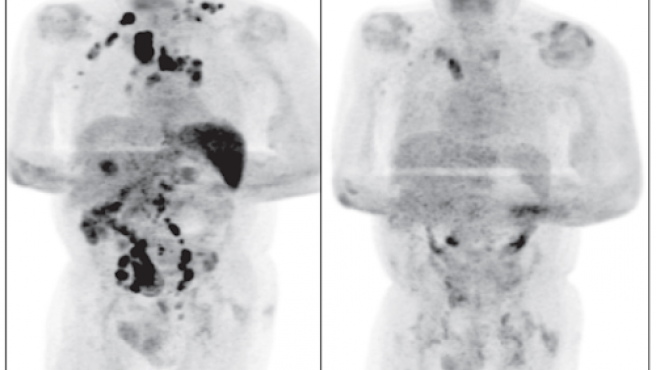

Cuatro meses después el paciente se sometió a la revisión del linfoma y los médicos comprobaron que se había producido una radical disminución del tamaño de los ganglios.

Estos mismo médicos que tratan al paciente han asegurado en su artículo del British Journal of Haemathology que la ingección por coronavirus "desencadenó una respuesta inmunitaria antitumoral, como se ha descrito con otras infecciones en el contexto del linfoma no Hodgkin de alto grado".